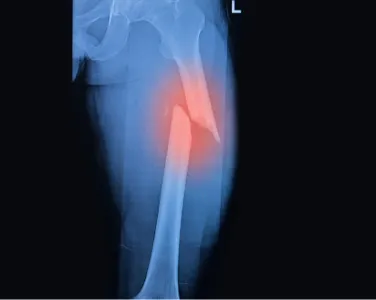

Fractures and Broken Bones

Stabilizing and repairing complex fractures to restore function and alignment.

Open Fractures

Specialized care for fractures where bone is exposed, reducing the risk of infection and promoting healing.